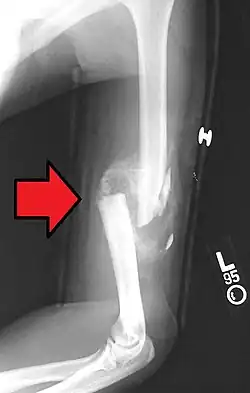

A displaced supracondylar fracture in a child

Distal humerus fractures usually occur as a result of physical trauma to the elbow region. If the elbow is bent during the trauma, then the olecranon is driven upward, producing a T- or Y-shaped fracture or displacing one of the condyles.[7]